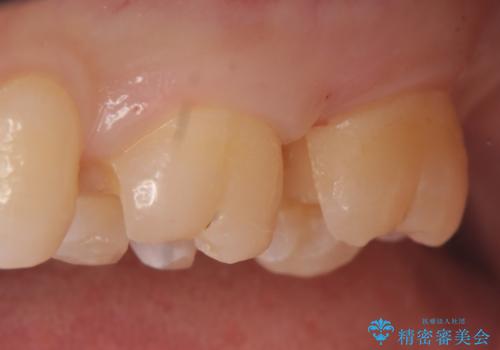

術後歯肉の回復を待ち、左下6、7ともにセラミックインレーによる修復を行いました。

当院のセラミックインレーはemaxという強度と審美性に優れた材料を使用しています。

またプレス方式でインレーを製作しているため、削り出しで製作するCADCAMより優れた適合性も持ち合わせており、虫歯が再発しにくい修復物です。